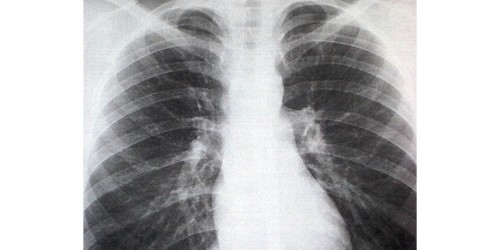

Back Ribs . Is this kind of beginning of emphysema Or is a cause of rib fracture internal bleeding. I am feeling better by every passing hour other wise with very mild or no pain conditions, but yet feel some rattling in my chest like cluck but with BASS and no treble . I am 63 but healthy . Should I go and see a lungs doctor Or a medical specialist Or orthopedist Or should pay the money in charity and enjoy the Medical Leave